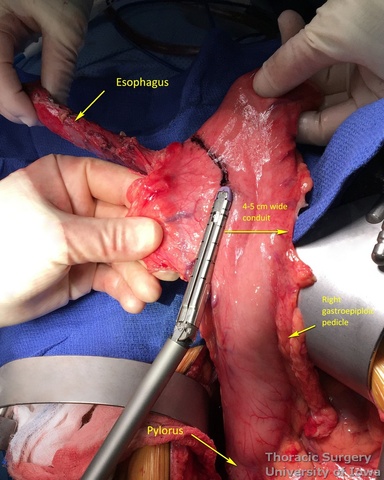

- At approximately the level of the third large vein (accompanying vagal “crow’s foot”) along the lesser curvature, lymphatic tissue and vessels are mobilized and divided to expose the gastric wall.

- Starting from the lesser curvature of the stomach, several stapler loads are sequentially fired towards the fundus of the stomach, thus creating a 4–5 cm wide gastric conduit and ensuring a 5 cm margin distal to the tumor. Depending on the thickness of the stomach, medium purple or thick black (alternatively blue or green, depending on manufacturer) loads are used.

- Gastric conduit should reach the cervical incision.